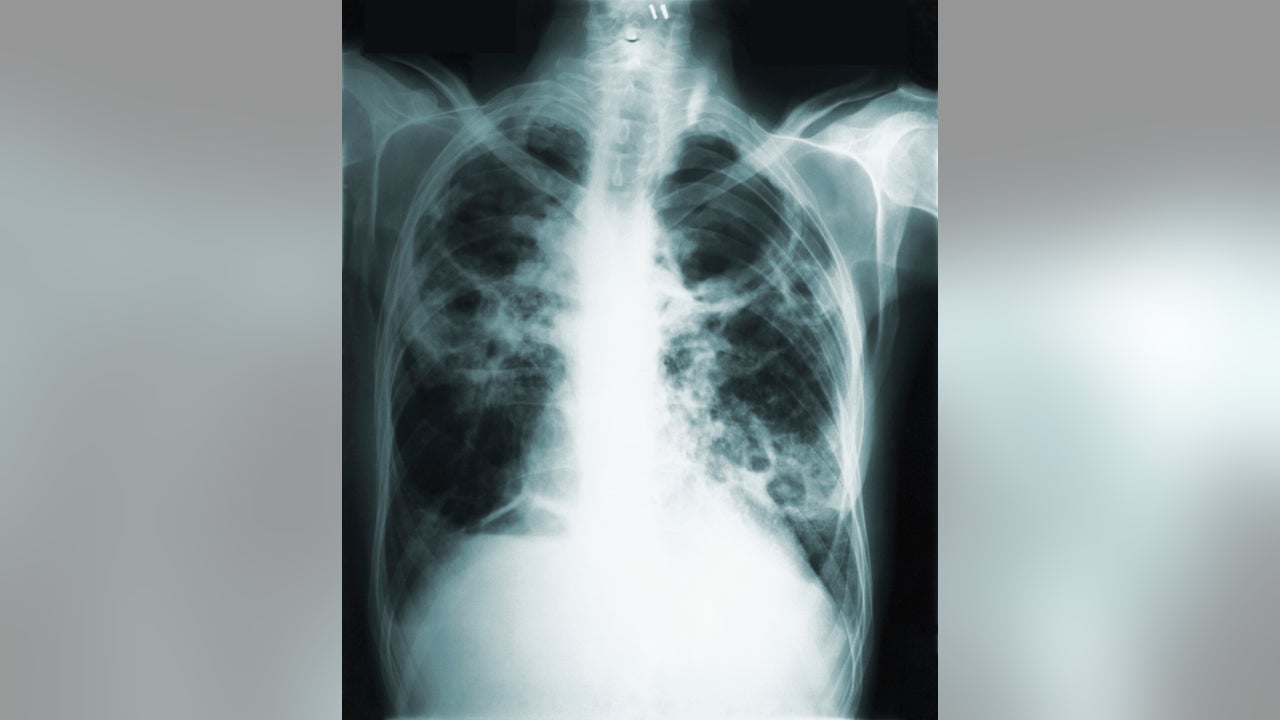

This 1966 image made available by the Centers of Disease Control and Prevention shows a chest x-ray of a tuberculosis patient. (CDC via AP)

An experimental vaccine proved 50 percent effective at preventing latent tuberculosis infection from turning into active disease in a three-year study of adults in Africa.

Doctors were encouraged because protection declined only a little after two years, and even a partially effective vaccine would be a big help against TB. The lung disease kills more than a million people a year, mostly in poor countries, and about one-third of the world's people harbor the bacteria that cause it.